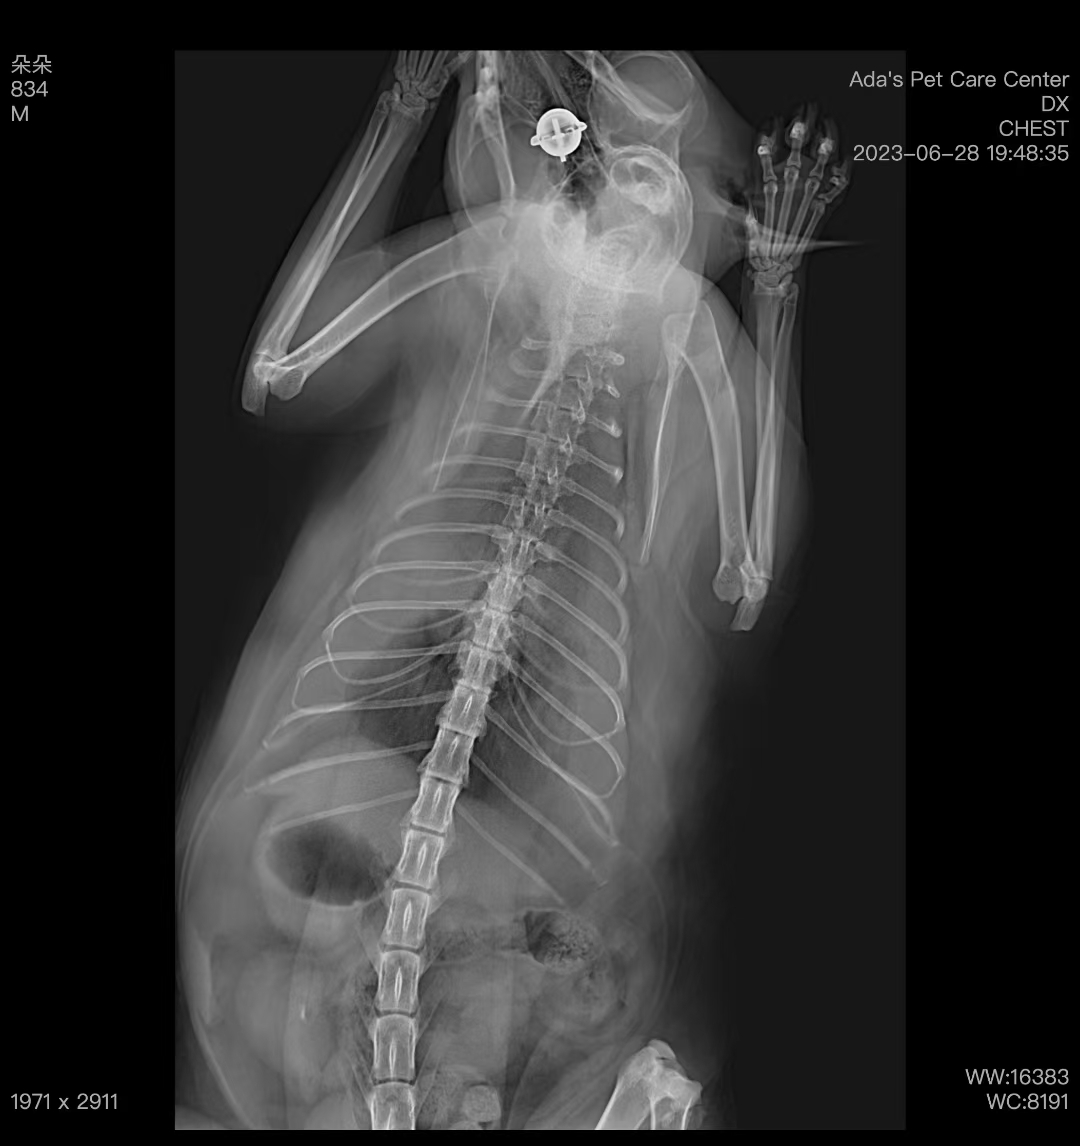

When the cat arrived, it was lethargic, struggling to breathe, and its tongue was purple. After oxygen therapy, its breathing improved slightly. We took an X-ray of the chest, which showed significant fluid buildup. We then performed a chest tap and drew about 200ml of yellowish fluid. After analysis, it was confirmed as chylothorax.